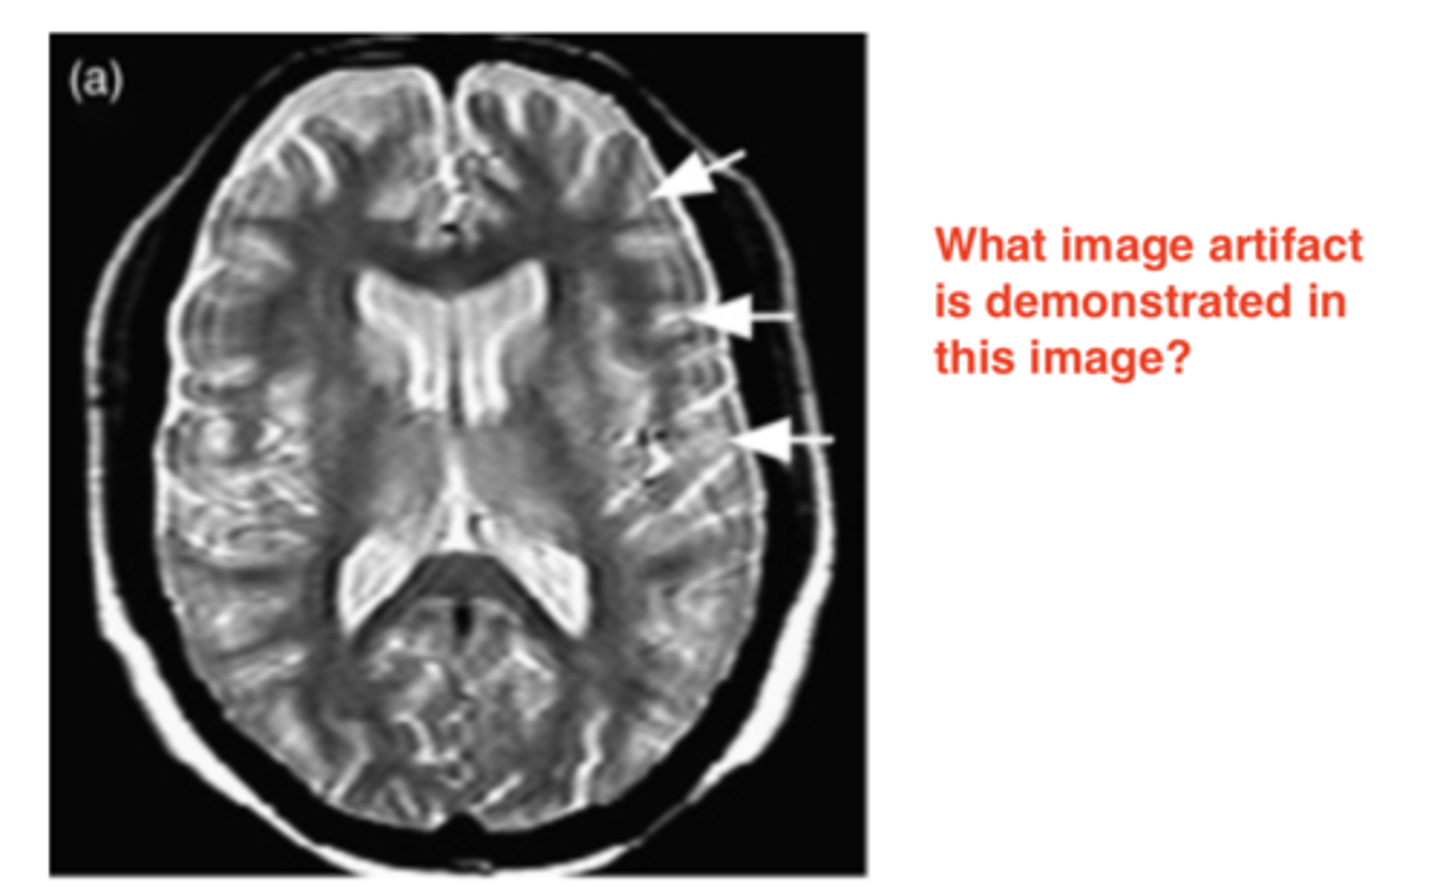

Zipper Artifact